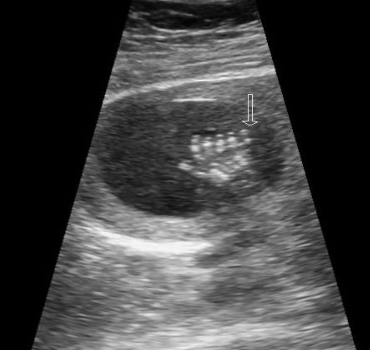

describe US evaluation of the spine in long

two curvilinear lines extending from the cervical spine to the sacrum

referred to as the railway sign

required images are C, T, L, S spine